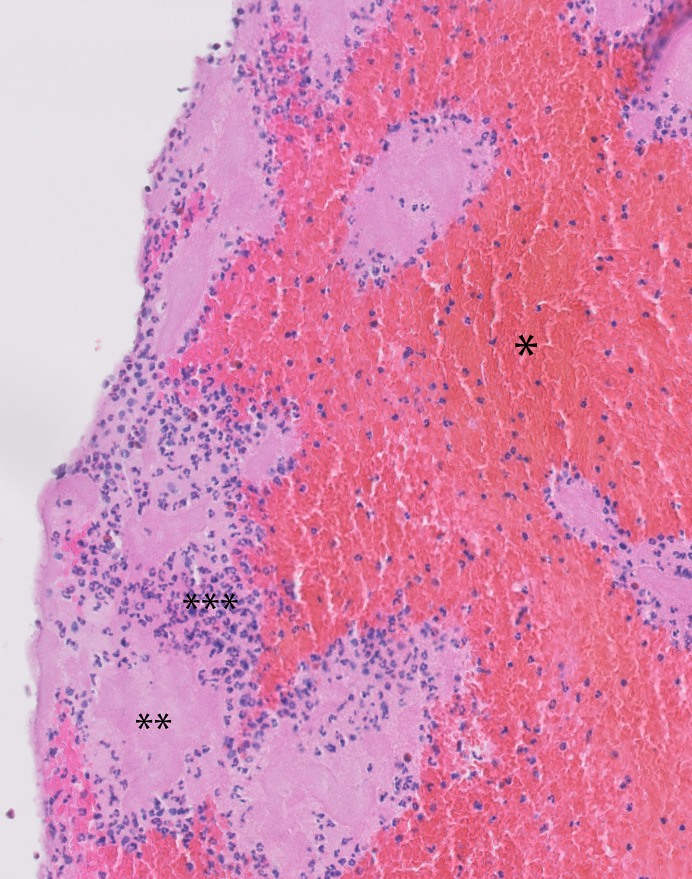

Methods: A total of 75 consecutive patients who presented to the Amphia Hospital with acute large vessel occlusion-related stroke and underwent MT were included in the study. The obtained thrombus materials were subjected to standard histopathological examination. Based on histological criteria, they were considered fresh (<1 day old) or old (>1 day old). Patients were followed for 2 years for documentation of all-cause mortality.

Abstract Image